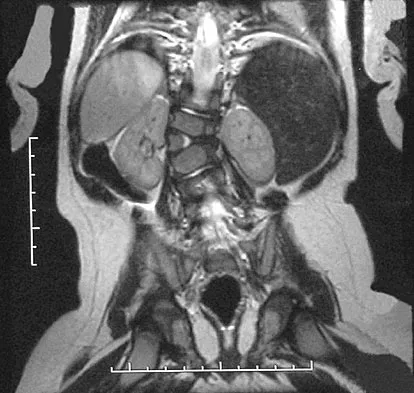

Question 48 High Yield

A 12-year-old boy reports the acute onset of pain and a pop over the right side of his pelvis while swinging a baseball bat during a Little League game. Radiographs reveal an avulsion of the anterior superior iliac spine with 2 cm of displacement. Management should consist of

Detailed Explanation